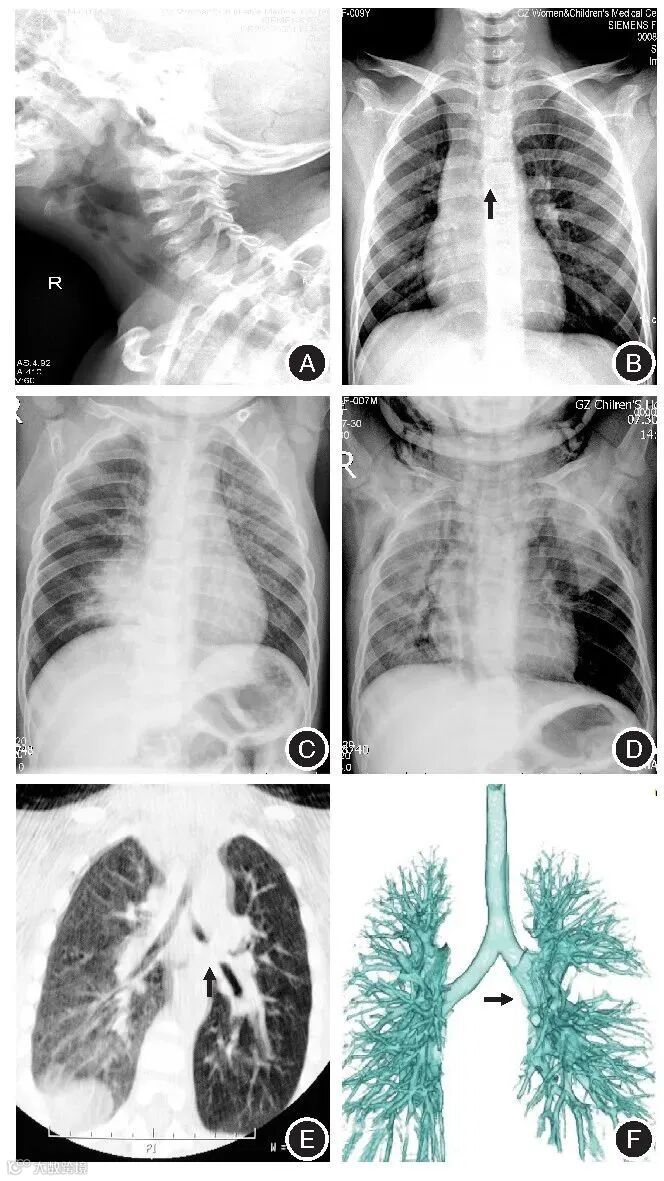

部分支气管异物案例影像

A:上气道异物——瓜子;

B:气管异物——硅胶管;

C:支气管异物——花生,间接征象:右侧阻塞性肺气肿并肺炎;

D:左支气管异物——瓜子,间接征象:肺气肿(肺野透亮),纵隔气肿,(腋区)皮下积气;

E:支气管异物——花生,左侧支气管内软组织(机化)密度影;

F:VR重建示左侧支气管气异物